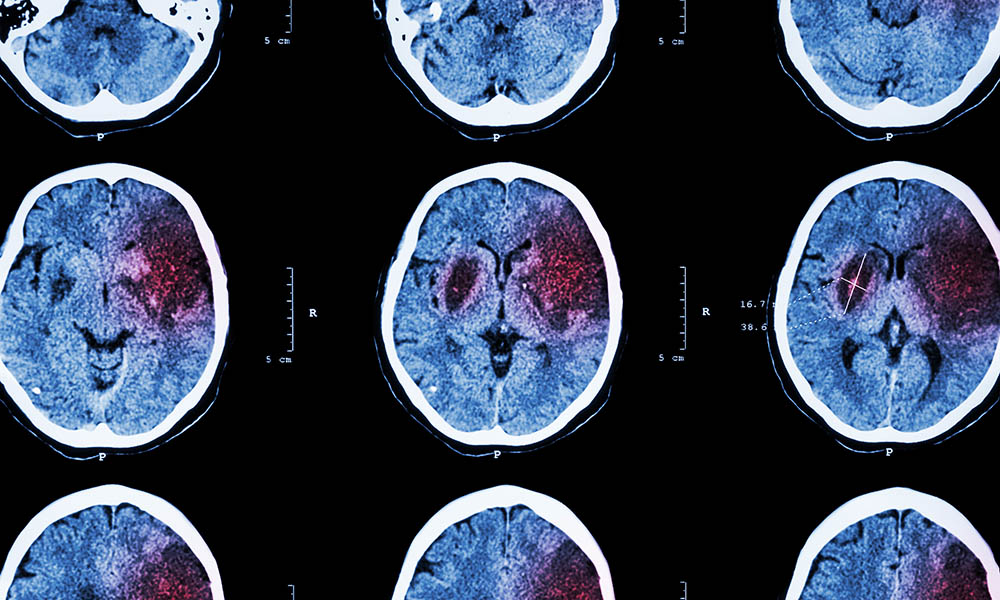

To ensure targeted therapy, it is necessary to establish whether the patient suffers from reduced blood flow or cerebral haemorrhage. This is usually done by imaging techniques, such as computed tomography (CT) and/or magnetic resonance imaging (MRI) of the brain.

A stroke disrupts the blood supply to the brain (due to reduced blood flow or a brain haemorrhage). The diagnosis is made by means of imaging techniques (CT, MRI), in addition to the clinical neurological examination.